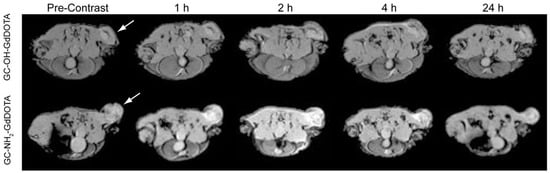

- Na, J.H.; Lee, S.; Koo, H.; Han, H.; Lee, K.E.; Han, S.J.; Choi, S.H.; Kim, H.; Lee, S.; Kwon, I.C.; et al. T1-weighted mr imaging of liver tumor by gadolinium-encapsulated glycol chitosan nanoparticles without non-specific toxicity in normal tissues. Nanoscale 2016, 8, 9736–9745. [Google Scholar] [CrossRef] [PubMed]